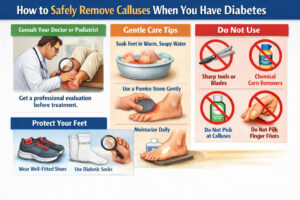

How to Safely Remove Calluses When You Have Diabetes (Without Risking Your Health) If you have diabetes and notice thickened,...

What Are Corns and Calluses? Let’s be honest—most people don’t think twice about thickened skin on their feet until it...